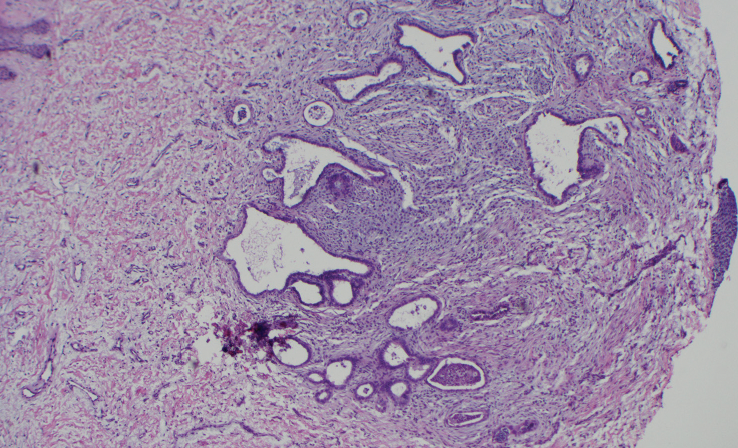

Histopathology

Histology reveals endometrial glands with apocrine-like secretion in a myxoid stroma.5 Extravasated erythrocytes and hemosiderin may also be seen.5

A shave biopsy of the lesion was performed, which showed a deep dermal nodule composed of apocrine glands in a myxoid stroma consistent with a diagnosis of cutaneous endometriosis (Figure 3 and Figure 4). The patient’s symptoms greatly improved following biopsy, and she was treated with a contraceptive implant by her primary care physician, which led to further symptomatic relief. She has not required further surgical intervention for her endometriosis and has not developed any new cutaneous lesions.

with active secretion, H&E stain, 400x magnification.